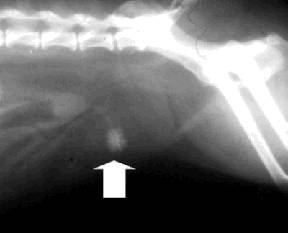

לפעמים הוטרינר יבצע צילום רנטגן כדי לוודא שאין אבן שניתן לראות בשלפוחית.

אבני סידן-אוקסלט בצילום רנטגן ובמיקרוסקופ

אבני סטרוביטים בצילום רנטגן